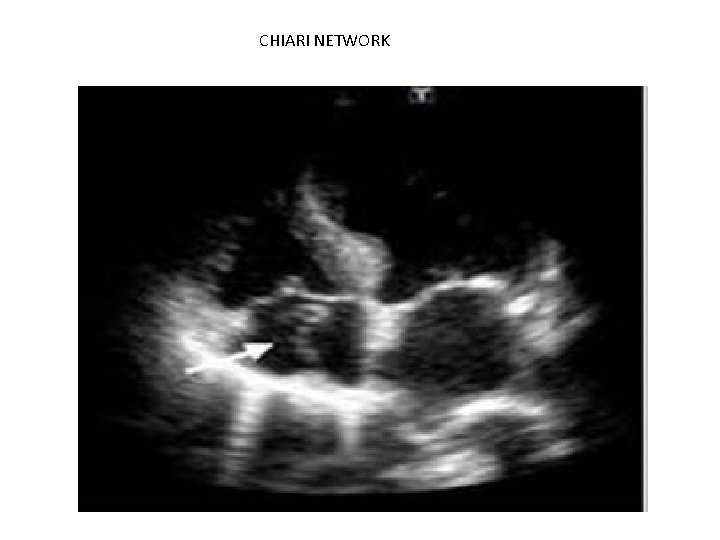

CHIARI NETWORK